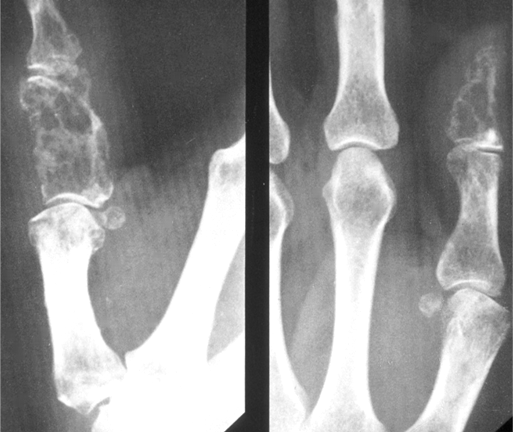

골 용해성 병변(Osteolytic)이 관찰된다면 : 신장암, 갑상선암, 위, 대장암 을 생각해 보아야 합니다.

(단발성 전이의 경우 신장암, 갑상선암에서는 전이 병소의 절제가 생존율 향상에 도움이 됩니다. 신장, 갑상선암은 혈관이 풍부하므로 선택적 동맥색전술을 예방적으로 하고 절제술을 하는 것이 안전합니다.)

전이성 골종양의 경우 영상과 같이 치료가 무척 어렵습니다. 지푸라기라도 잡는 마음으로 방사선치료와 항암화학요법을 할 수 있습니다. 5년 생존율이 높아 보이는 환자군에서 장관골과 골반골의 임박 골절, 병적 골절 에는 예방적 고정술을 해볼 수 있습니다. (RT에도 효과가 없고, 2.5cm 정도로 큰 사이즈와 cortex가 50%이상 파괴되어 부러지기 직전일때, 소전자의 견열골절이 있을때 = Mirel 8점이상)